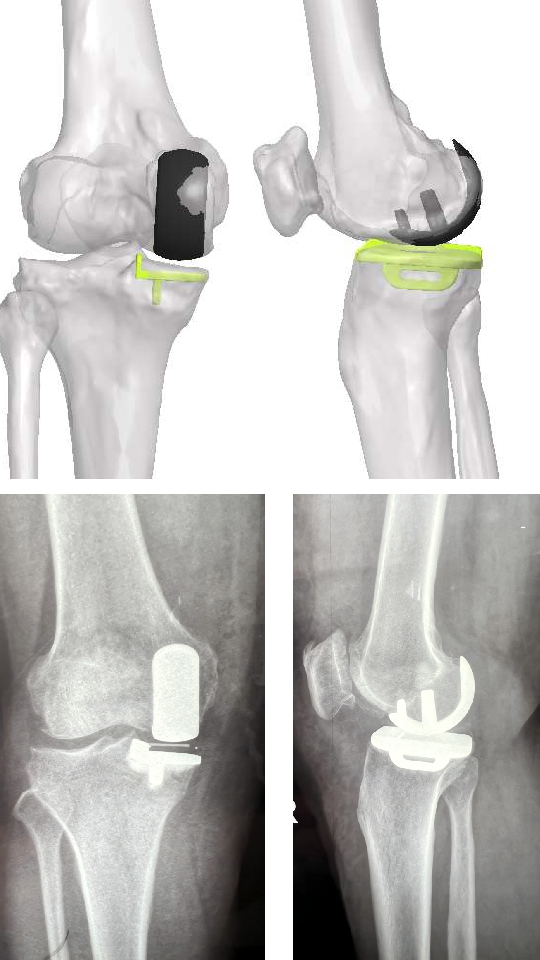

图片

不同案例——导板术中应用